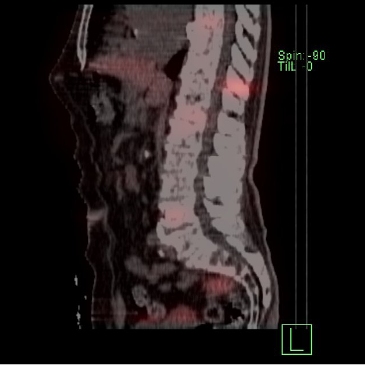

/ Obr. č. 3: SPECT/CT za 4 hod. po aplikaci OctreoScanu. /

Popis: pozorujeme patologicky zvýšenou depozici radiofarmaka:

- v několika fokusech skeletu (nejkontrastněji v proc. spinosus Th10, dále v hrotu pyramidy os temporale vlevo, tělech Th3, Th6, Th8, Th12, L4, kosti kyčelní vlevo), vícečetně v žebrech oboustranně, v ldCT obraze mnohočetná smíšená převážně sklerotická ložiska

- nehomogenní kumulace v játrech, místy až s fokusy, nejnápadnější je v levém laloku ventromediálně

- v ložisku v malé pánvi pararektálně vlevo vel. cca 48x38mm